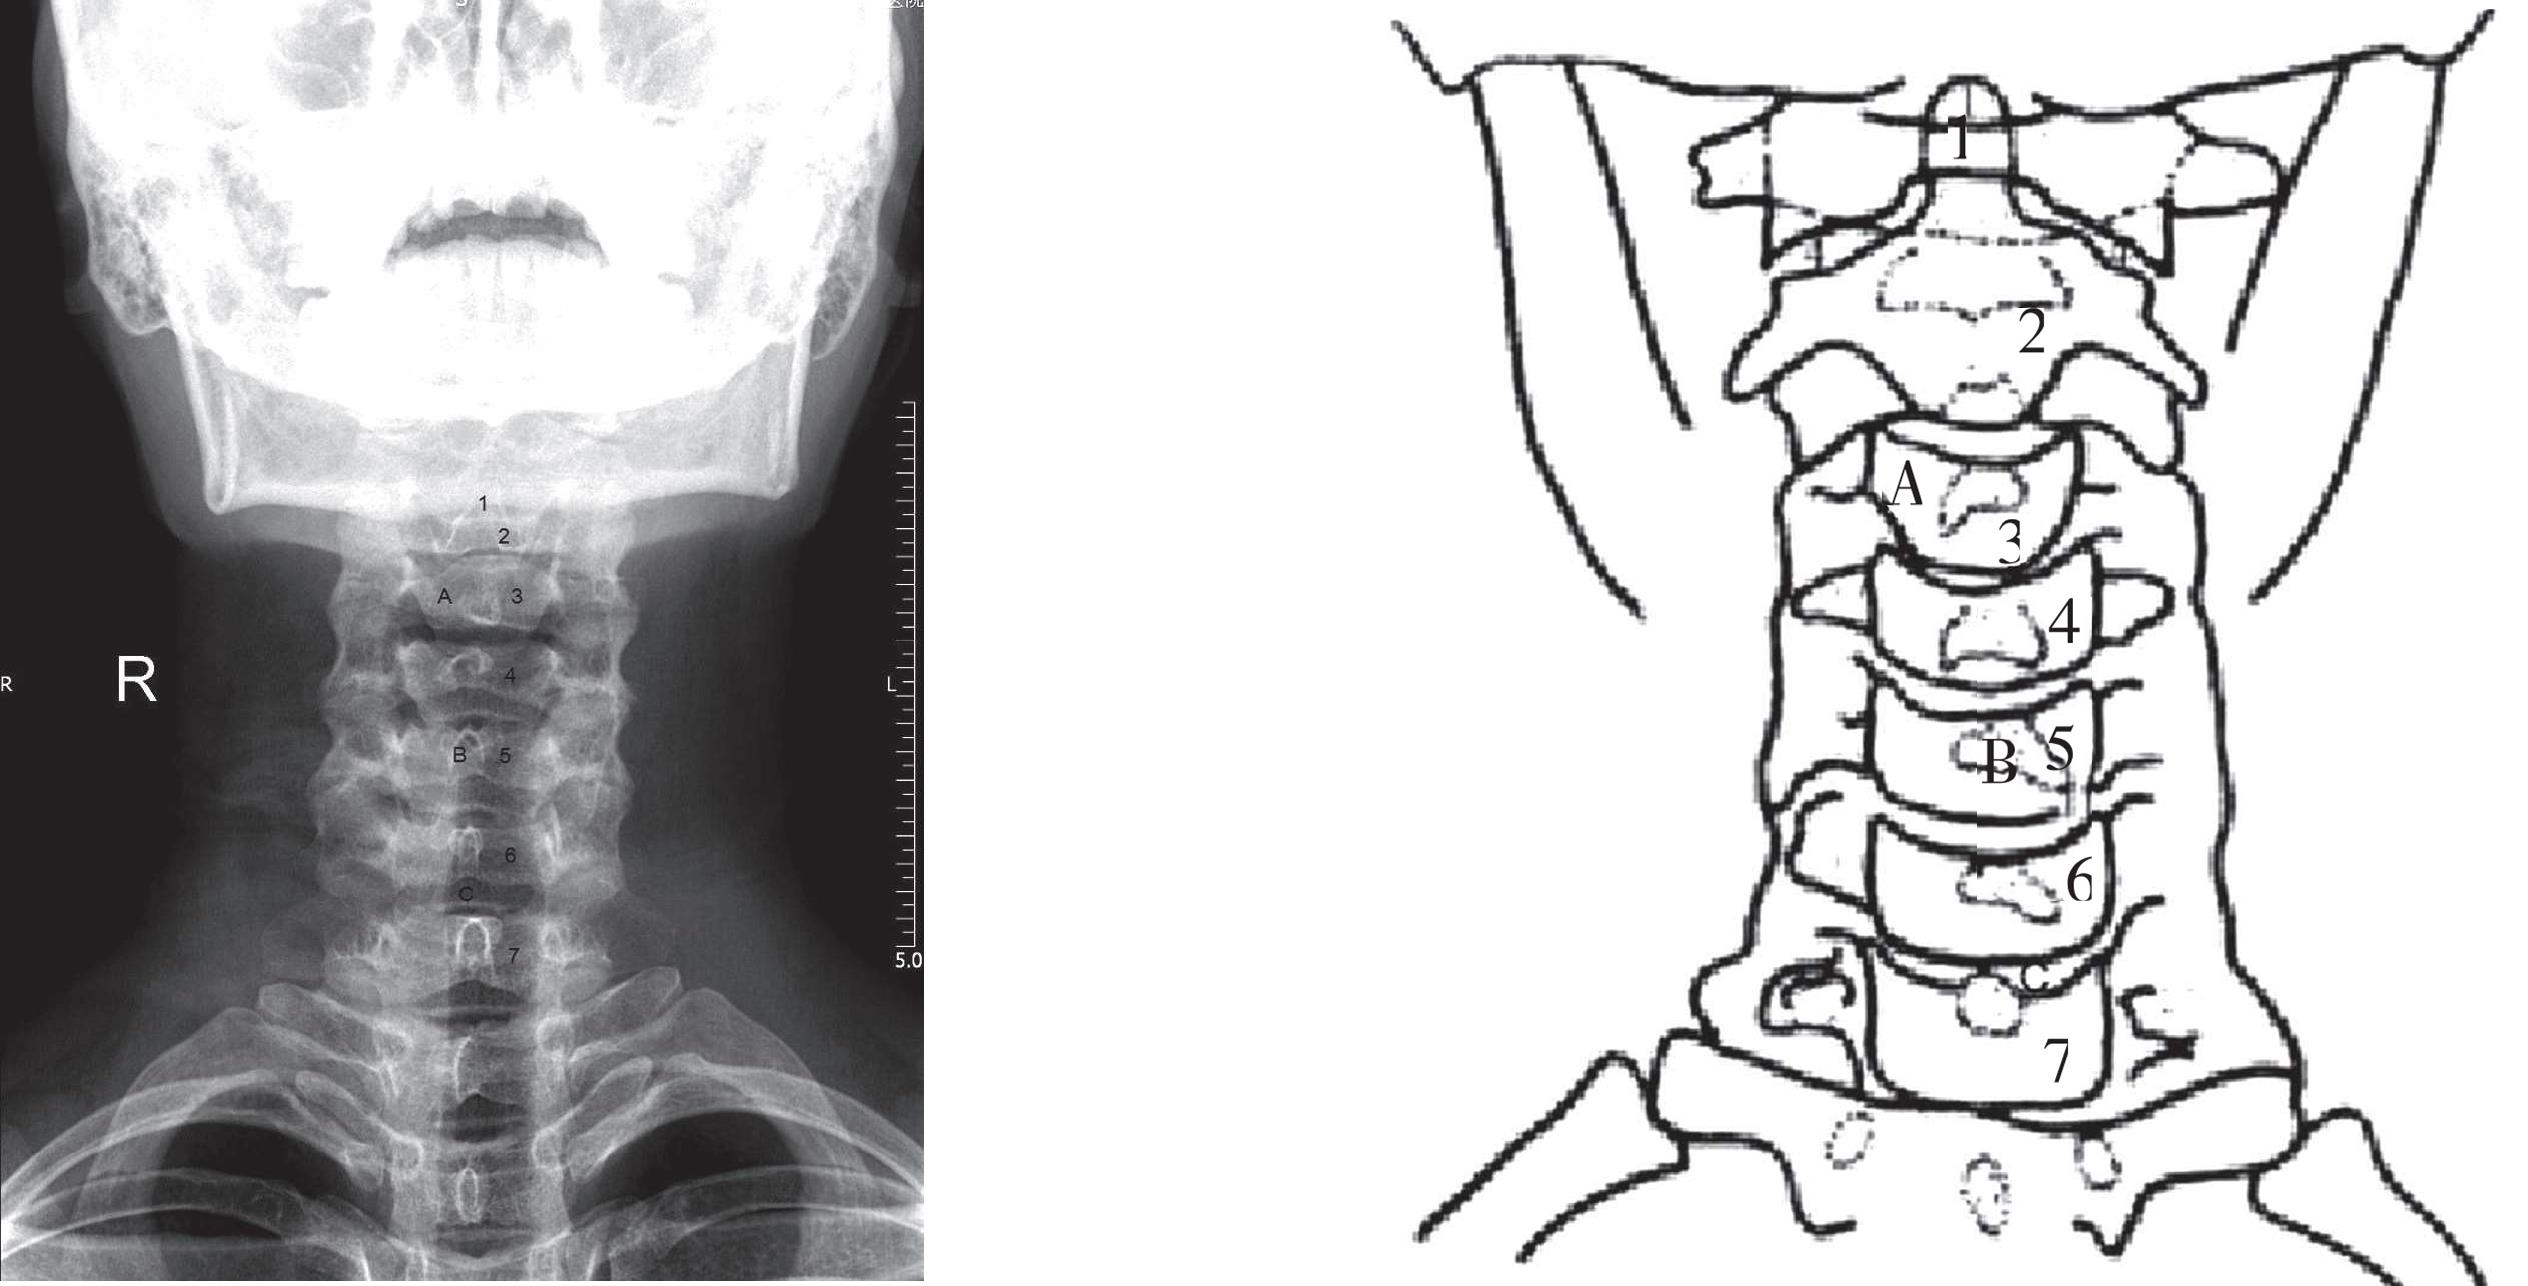

患者站立或仰卧于摄影台上,双臂下垂于身旁,身体正中矢状面与台面垂直,并与台面中线吻合,头微向上仰,使听鼻线垂直于台面,中心线指向C 4 (或甲状软骨),并向头侧倾斜15°~20°。胶片上缘包括外耳孔平面,下缘至颈静脉切迹(图3-1),患者平静呼吸下屏气曝光。X线片可清晰显示C 3 ~C 7 椎体、椎间盘间隙及钩椎关节。棘突投影于正中线上,与椎体相重叠,呈卵圆形。横突骨质清晰,向左、右突出。椎弓根呈轴位投影于椎体与横突相接处(图3-2)。在C 3 ~C 7 颈椎前后位基础上略加改动,便可使C 1 ~C 7 颈椎在一张照片上显示:①听眶线垂直于台面;②中心线垂直投照,入射点在C 4 上3cm处;③曝光时屏气,头颅必须保持固定,下颌快速做张闭口活动,此时C 1 ~C 2 背景模糊如体层片,椎体轮廓和骨质皆能清晰显示。

A. 椎体;B. 棘突;C. 椎间隙;1. 齿突(C 2 ~C 7 椎体上标有数字)

图3-2 颈椎正位片

颈椎前后位X线片示:棘突位于正中线上,横突位于椎体两侧,椎弓根呈轴位投影于椎体与横突相接处,横突和棘突之间为椎板和椎弓前后平面,椎弓断面上下示关节突。